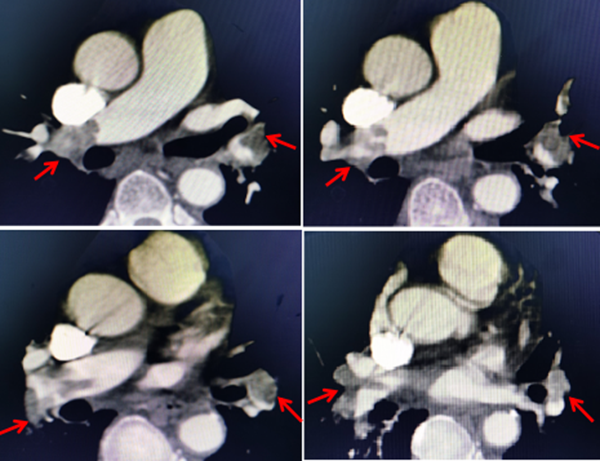

圖一:肺動脈CTA示:左右肺動脈主干及各級分支栓塞

急診科團隊通過臨床表現(xiàn),體檢及即刻床邊超聲,第一時間作出“急性肺動脈栓塞”初步診斷,立即啟動院內胸痛救治綠色通道。當即急診科、放射科、超聲科等科室緊急就位,立刻完善主肺動脈CTA、血氣分析、心臟彩超、雙下肢動靜脈彩超檢查。迅速明確診斷:急性肺動脈栓塞,右下肢靜脈血栓,呼吸衰竭,休克?;颊卟∏槲<?,治療刻不容緩。急診科 、血管外科、麻醉科及心臟外科等科室緊急聯(lián)合會診決定行介入外科相結合Hybrid一站式下腔靜脈濾器植入+胸正中切口體外循環(huán)下肺動脈切開取栓術。